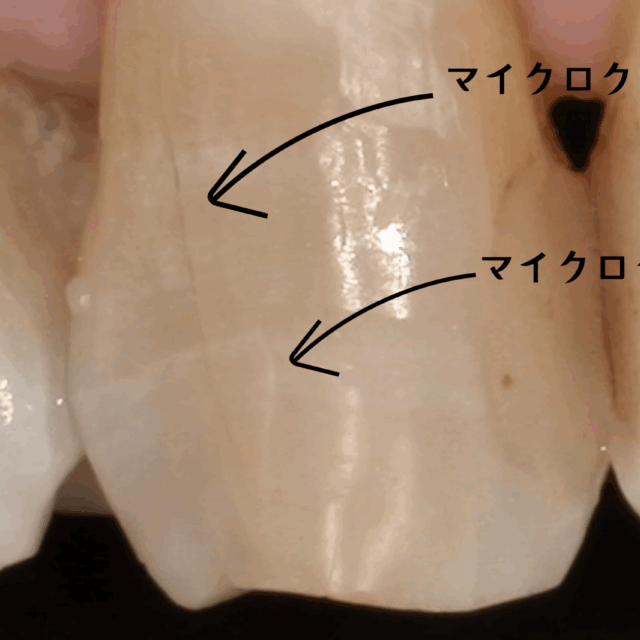

特性③:表面に傷がつきやすく「細菌が付着しやすい」

柔らかいということは、歯ブラシによる日々の清掃でも、表面に微細な傷がつきやすいという面もあります。 治療直後はツルツルだった表面も、数ヶ月、数年と経つうちにザラザラになり、その微細な傷に細菌(プラーク)が付着しやすくなることがあります。

プラスチックの表面にこびりついた汚れ(バイオフィルム)は、歯磨きでは落としにくい場合もあります。 つまり、保険のプラスチック系材料の被せ物は、細菌が付着しやすい環境を作り出してしまう可能性があるのです。

その結果、歯と被せ物の境目に微細な隙間(マイクロリーケージ)が生じやすくなり、そこから唾液と共にむし歯菌が内部に侵入する可能性が指摘されています。

- マイクロスコープ(歯科用顕微鏡): 当院では、すべての治療にマイクロスコープを使用します。肉眼の最大20倍まで視野を拡大することで、むし歯の取り残しを確実に防ぎ、歯と被せ物の境目をミクロン単位で精密に仕上げます。肉眼での治療は「勘と経験」に頼る部分も大きいですが、顕微鏡治療は「確実な診断と処置」を可能にします。